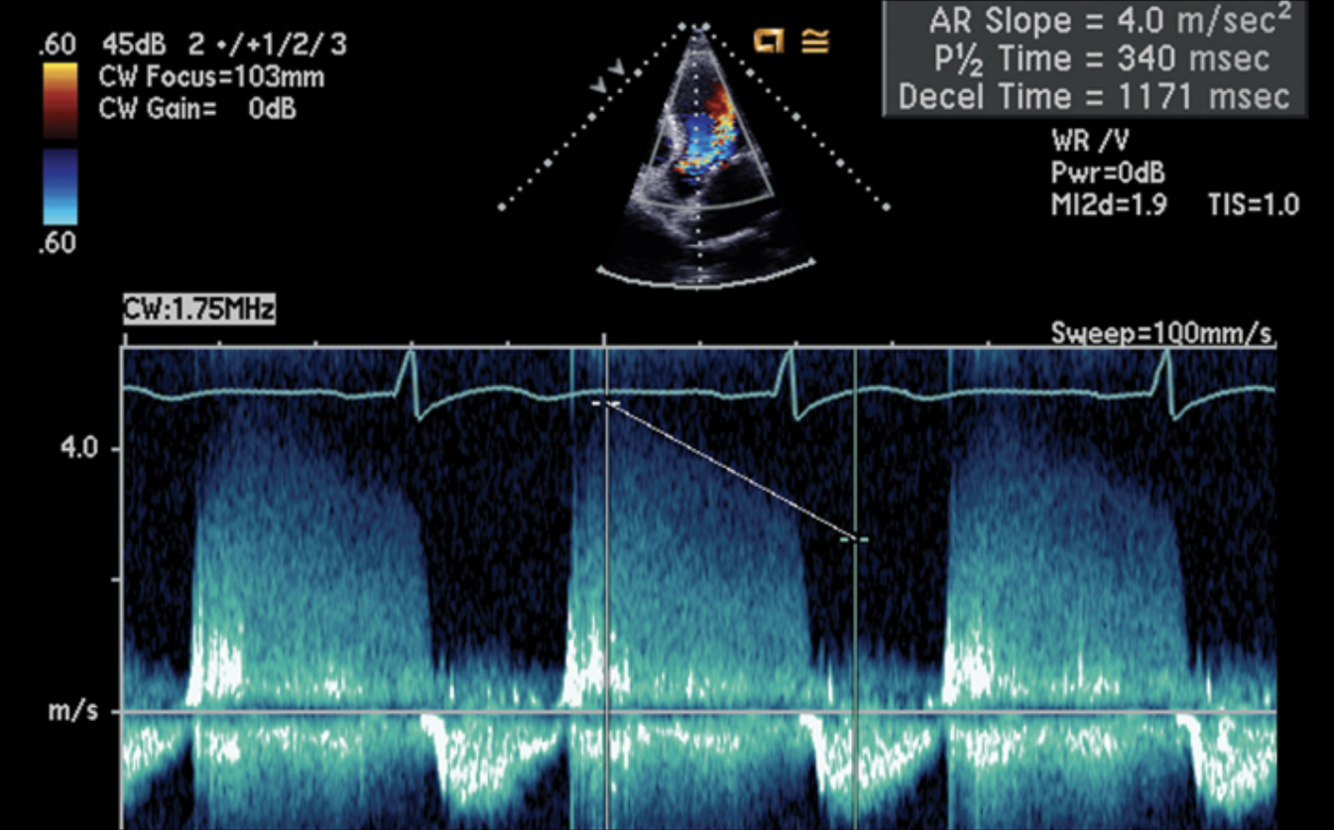

Define AR pressure half-time?

measure of how quickly the aortoventricular pressure gradient equalizes during diastole

What are two factors that may influence PHT in AR?

Describe the severity scale in diagnosis of AR:

**Obtained using CW doppler